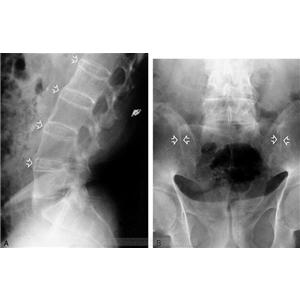

强直性脊柱炎

AS ①晚期 ②重度 病史:5年+

治疗后骶髂关节疼痛消失,腰椎前屈、背伸侧弯活动自如,膝关节无压痛感,复查血沉、C反应蛋白、等各项检查均已达到临床康复的标准。